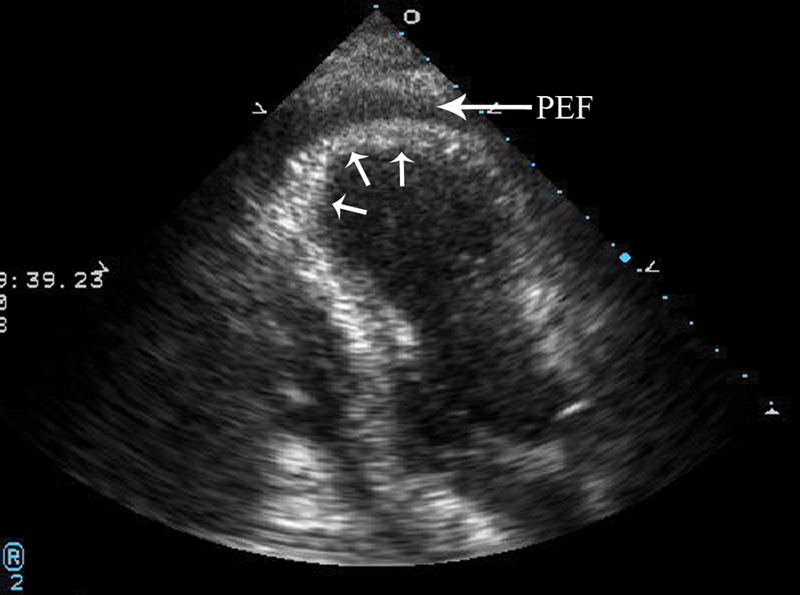

فحوصات تشخيصية لبعض امراض القلب والشرايين التاجية